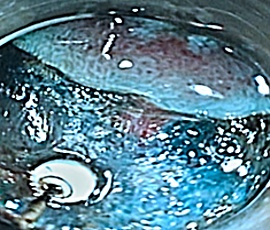

病変範囲の確認

マーキング